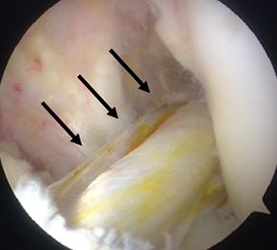

関節鏡視下前十字靭帯再建術(ACL再建術)

当院では、年間50例前後の前十字靱帯再建術を施行し、プロからレクレーションレベルまで幅広く対応しております。本手術は内視鏡を用いて行うため、少数の小さい傷で行う事ができます。膝の屈筋腱(半腱様筋腱と薄筋腱)を採取し、解剖学的に正常に近い靱帯再建術を低侵襲な手法で行っております。手術時間は、ほぼ全ての症例において1時間半以内(平均74.3分)です。術直後の痛みは、麻酔科の協力により良好にコントロールされます。靱帯再建術後はリハビリが大変重要です。当院では、再断裂防止を念頭におき、スポーツ復帰に向け準備を進めて参ります。主な術後合併症の一つである感染の発生率は0%です(2012年4月から2018年3月までの間に本手術を施行した266例中)。